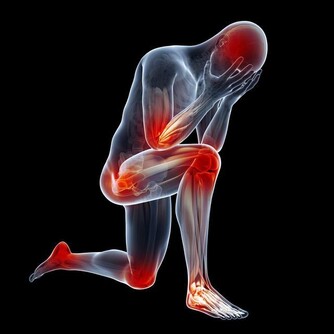

※急著開空調:室外氣溫很高時,如果將空調溫度調得很低,在冷熱兩種環境轉換時,人體會有應激反應。比如血管突然收縮,可能引發心梗、中風等急症;肌肉筋膜痙攣,誘發肩背痛等。可以適時拿電扇出來給身體降降溫,另外要注意別長時間待在空調房裡。